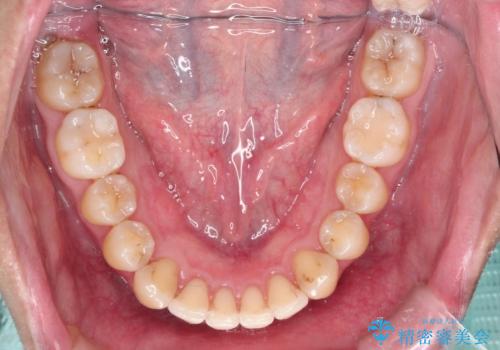

- 前歯の凸凹を主訴に来院された患者様です。

インビザラインにて治療を行いました。

- 1年6ヶ月